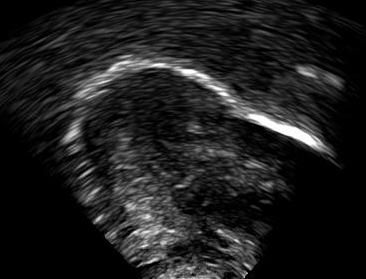

Ultrasound tongue imaging provides a non-invasive means for assessing tongue position and movement during speech production. However, the presence of speckle noise and irrelevant high contrast edges often degrades the usability of ultrasound images by obscuring the tongue surface [1]. Consequently, extracting tongue contours from ultrasound images remains a non-trivial task.

6 Error analysis

As the CNN is trained to identify the white edges directly corresponding to the tongue surface, additional or missing white edges due to bad image quality or speaker physiology can lead to failures in identifying parts of the tongue surface. In the absence of prior knowledge of plausible tongue shapes, the model will sometimes generate tracking errors when the white edge becomes blurry or interrupted. Similarly, bright edges in the image background are likely to be recognized as part of the tongue; tongue contours generated from image frames with these edges will likely suffer from implausible curvatures as interpolation in post-processing attempts to connect these regions. There some potential solutions to these problems, including incorporating temporal constraints on tongue contour variations across frames [3], or adding a smooth constraints that penalizes discontinuity of tongue contours, or introducing a strong prior probability of possible tongue locations. In data processing, these issues can also be mitigated by tuning the parameters in post-processing to match the needs of the specific dataset, and remaining errors can also be addressed through manual correction (as even then, the workload is considerably reduced relative to manually labeling all frames).